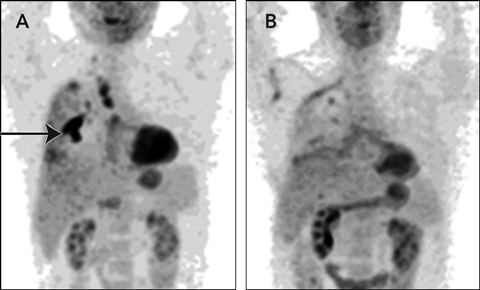

The patient remained well on follow-up. His lung function improved and, despite dyspnoea during exercise, he walked 20 km per week. Serial chest radiographs showed significant pleural thickening but no other abnormality. However, as the cause of the pleural effusion remained undiagnosed, the serum soluble mesothelin-related protein (SMRP) level was measured. At 2.8 nM, it was higher than the reference range (< 2.5 nM),1 suggesting malignant pleural mesothelioma (MPM). The biopsy specimens collected at presentation were reviewed, but no evidence of malignancy was found. A combined positron emission tomography/computed tomography (PET/CT) scan revealed intense tracer uptake (Box, A), suggesting MPM involving the pleura at the right lower lobe and apex, with minimal uptake in the paratracheal and subcarinal lymph nodes. Results of all other investigations (eg, full blood count, liver function tests, and measurement of creatinine and blood glucose levels) were normal.

The patient recovered well and returned to part-time work. Some residual neuropathic pain arising from the thoracotomy scar was controlled with medication. One year after surgery, a repeat PET/CT scan showed no residual tumour or uptake of tracer in the lymph nodes (Box, B), and the SMRP level was within the reference range. He remained well 19 months after surgery.